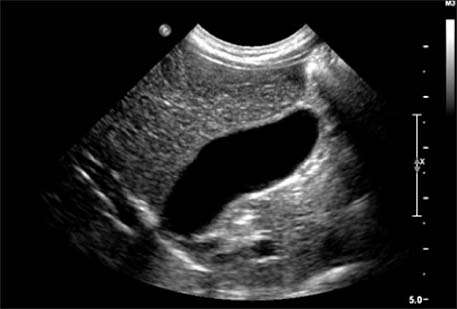

Ultrasonography performed at the emergency room shows multiple gallbladder sandy stones with sludge (case 2).

jkaps-20-62-g002.jpg